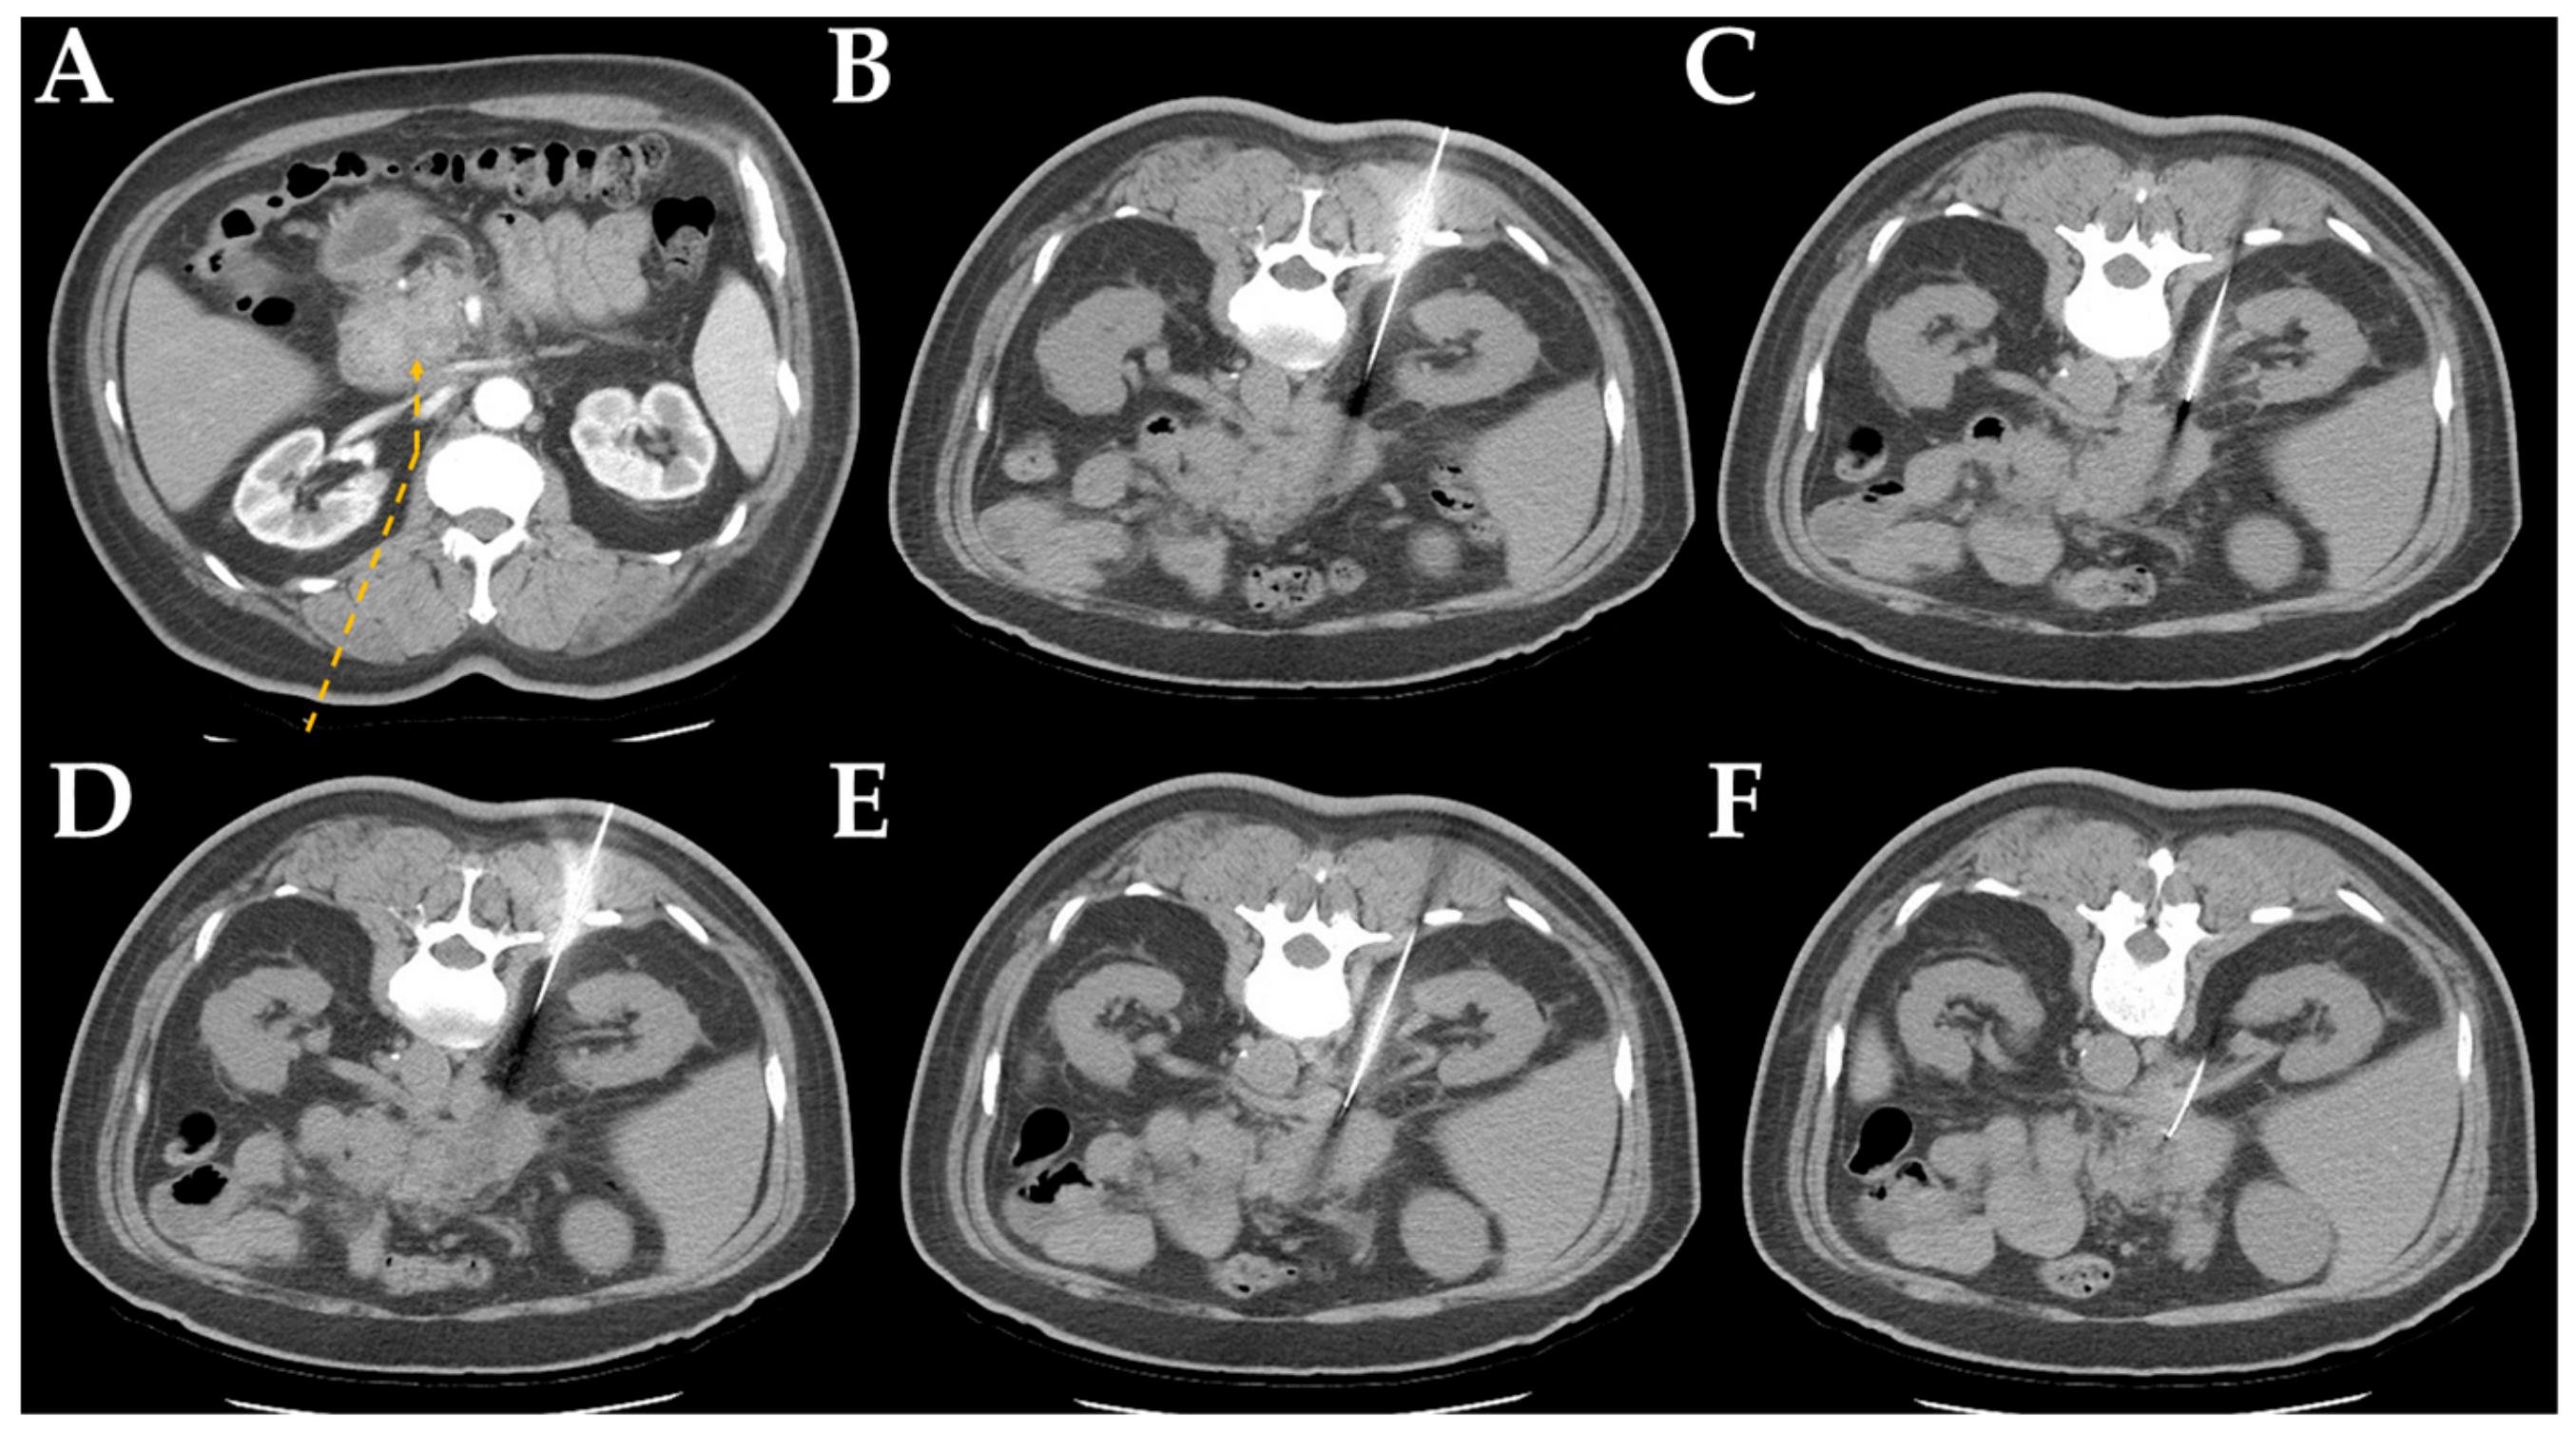

2.2. Computed Tomography-Guided Core Needle Biopsy Technique

| Detour route 1 | 169 | 29 (14–54) |

| Detour route 2 | 169 | 28 (12–51) |

| Detour route 3 | 26 | 28.5 (17–42) |

| Detour route 4 | 19 | 29 (16–41) |

| Detour route 5 | 26 | 29.5 (19–40) |

| Detour route 6 | 11 | 28 (19–38) |

| Detour route 1 | 26 | 49 | 43 | 51 | 169 (40.2%) |

| Detour route 2 | 16 | 32 | 39 | 82 | 169 (40.2%) |

| Detour route 3 | 2 | 4 | 3 | 17 | 26 (6.2%) |

| Detour route 4 | 0 | 2 | 6 | 11 | 19 (4.5%) |

| Detour route 5 | 3 | 10 | 6 | 7 | 26 (6.2%) |

| Detour route 6 | 0 | 6 | 2 | 3 | 11 (2.6%) |